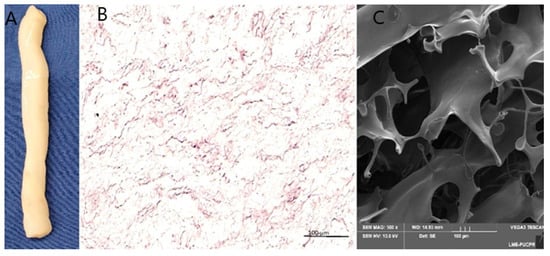

To evaluate the decellularization process, Wharton’s Jelly (WJ) was histologically analyzed using hematoxylin and eosin (H&E) staining and scanning electron microscopy (SEM) (Figure 2B,C). The results demonstrated the efficient removal of host cells and cellular fragments, with no visible nuclear residues. Additionally, the integrity of the mucous connective tissue structures and collagen fibers was preserved.

Figure 2.

After decellularization, (A); Macroscopic observation of decellularized Wharton’s Jelly (WJ), which were evaluated with hematoxylin–eosin (HES) staining of paraffin-embedded sections (scale bar = 200 µm), (B); The structures were characterized with scanning electron microscopy (SEM) (scale bar = 100 µm), (C).

In our study, the decellularization of Wharton’s Jelly was confirmed by hematoxylin–eosin (HE) staining and scanning electron microscopy (SEM), demonstrating the complete removal of cells from the tissue. These results indicate that the preserved extracellular matrix of Wharton’s Jelly can serve as a suitable structural support for cell retention and tissue regeneration. The absence of cells in the decellularized material minimizes potential adverse immune responses and allows its safe application as a biological scaffold for cardiac tissue engineering.